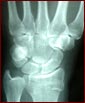

What are the most common skating injuries? Probably wrist injuries for skaters, I would have thought. When you fall, you automatically put out your hands to protect yourself, and as a result they tend to take most of the force. Ankles are pretty common as well, for riders and skaters, it's the same as before when you come off and land on your feet.